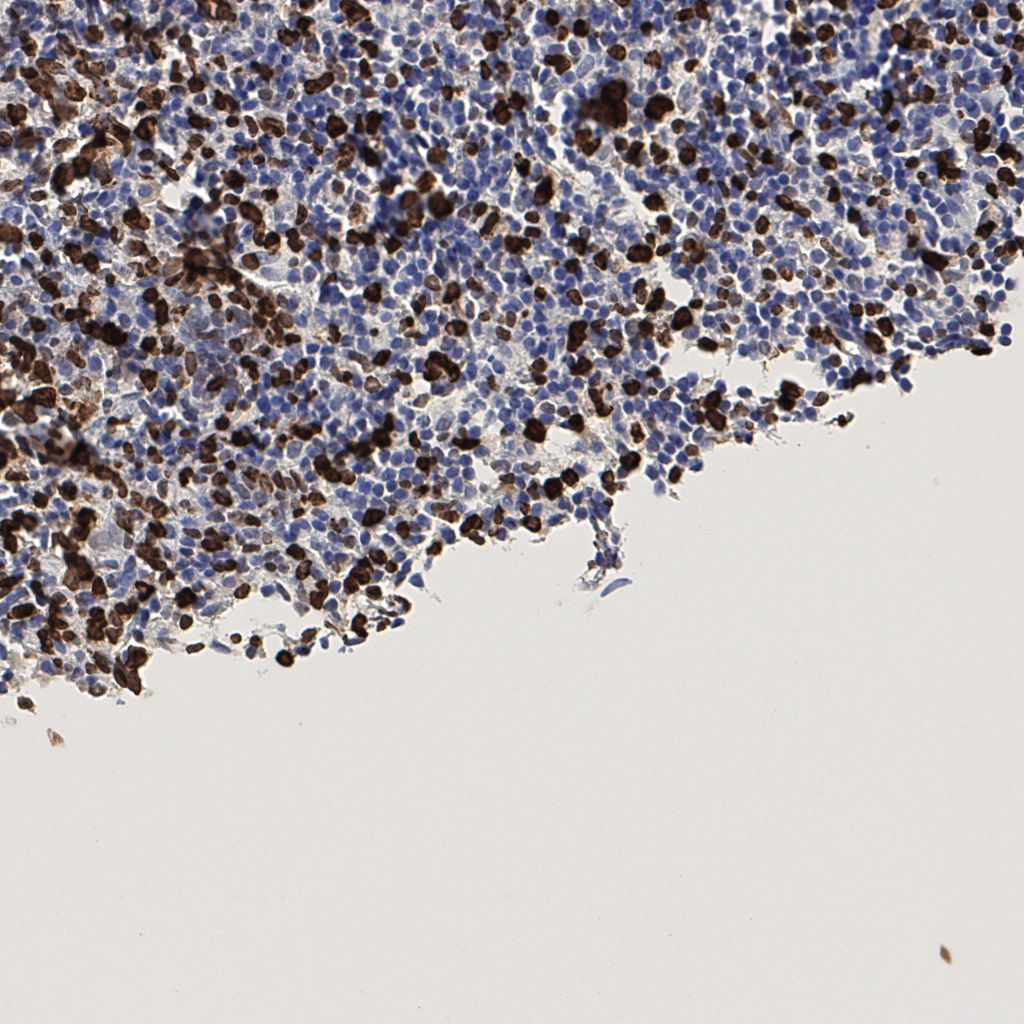

7.85%

Ki67 指数

阴 1104

阳 94

标记后

标记前